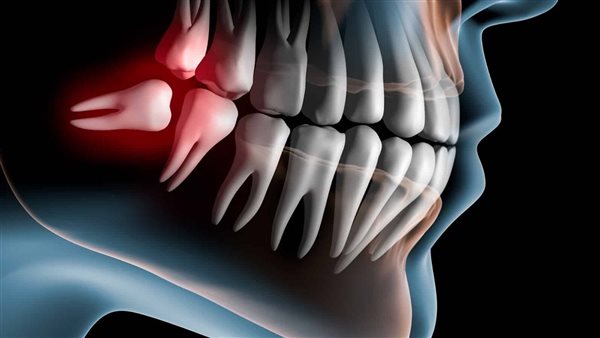

كشف الدكتور محمد أبو السعود، أخصائي زراعة الأسنان عملية خلع ضرس العقل المدفون بنج كامل، مشيرا إلى أن الطبيب يجري ثقوبا صغيرة في اللثة، مع إزالة جزء من العظام المحيط بالسن، بهدف الوصول إلى ضرس العقل المدفون.

وأضاف أخصائي زراعة الأسنان، أن عملية خلع ضرس العقل المدفون بنج كامل، تستغرق وقتا يصل إلى ساعة أو أكثر، حيث يجري الطبيب بعد الانتهاء من خلع الضرس خياطة لمكان الجرح، مشيرا إلى أن هناك حالات تستدعي خلع ضرس العقل جراحيا، وهي تكون كالآتي:

- إذا كان الشخص يعاني من جذور شديدة الانحناء لضروس العقل.

- وأيضا إذا كان ضرس العقل مكسورا بدرجة كبيرة.

- وأخيرا إذا كان الضرس مدفونا.